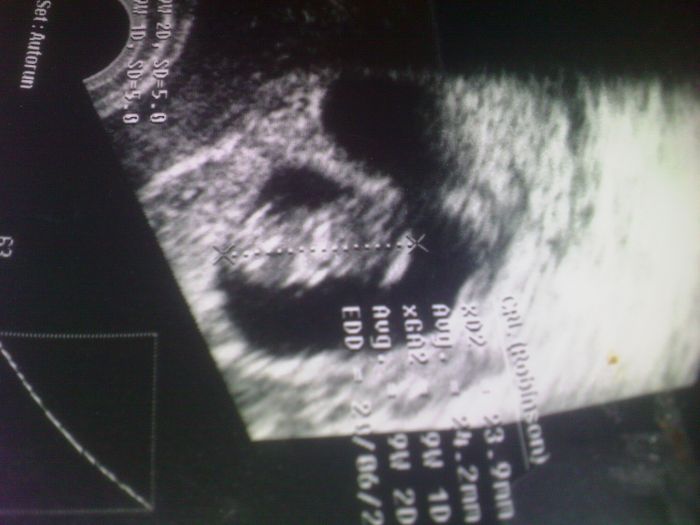

Ahojik Holky tak mam po kontrole miminko je zdrave videla jsem sredicko aj karticku jsem i dostala.Posilam Fotecku.

Moni taky mas krasne miminko no me dal dnes karticku a to jsem 9+0tt.